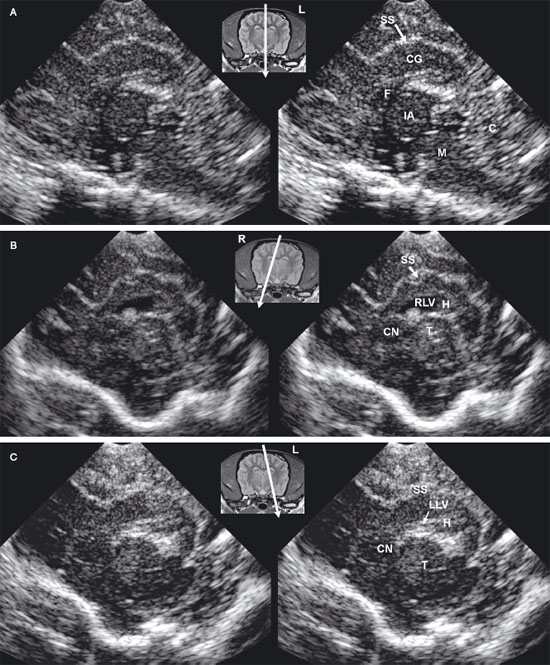

Longitudinal images made near the midline are true sagittal images, but when the probe is moved past the edge of the fontanel, the probe must be angled to enable the beam to reach the lateral margins of the brain. The floor of the cranium appears curved in images showing the lateral portions of the brain, whereas the floor of the cranium is more irregular in images made near the midline (midsagittal images). As the probe is angled laterally, structures that are anatomically closer to the midline appear in the near field of the ultrasound image, whereas more lateral structures are seen in the far field (Figure 1.4).

The interthalamic adhesion and, more caudally, the mesencephalon can be seen in midsagittal images as hypoechoic structures surrounded by echoes created mainly by choroid plexus in the third ventricle and meninges and in vessels in the subarachnoid space. In some areas, the third ventricle will appear anechoic or hypoechoic because of the presence of CSF. The osseous tentorium is incompletely ossified in neonates, enabling visualization of hyperechoic echoes created by the vermis in the posttentorial area of the brain. More superficially, the callosal sulcus is seen as a hyperechoic line. The corpus callosum has an appearance similar to that seen in transverse images. It is hypoechoic, with a deep hyperechoic interface.

When the probe is angled to obtain a lateral parasagittal image, the subarachnoid space and third ventricle are no longer seen; the thalamus and lateral ventricle are now visible on the imaged side. The thalamus appears as a hypoechoic structure outlined by hyperechoic choroid plexus in the lateral ventricle. Areas of the lateral ventricle with sufficient CSF may appear anechoic or hypoechoic. The caudate nucleus is imaged rostral to the thalamus as a hypoechoic structure with increased echogenicity superficially. This structure is more apparent in older dogs than in neonates. The thalamocaudate groove is seen between the thalamus and caudate nucleus. This groove is more apparent in older dogs, but in neonates a hyperechoic clump of choroid plexus is often seen in the lateral ventricle in this region. Care should be taken not to mistake this normal appearance for intraventricular hemorrhage that is also hyperechoic. In lateral parasagittal images, the splenial sulcus is seen in addition to the callosal sulcus and corpus callosum and appears as an undulating hyperechoic line. The cingulate gyrus shows as a hypoechoic structure deep to the splenial sulcus.

The feline brain can be evaluated by using transverse and longitudinal sonographic planes (Figures 1.5 and 1.6).

The lateral ventricles are slitlike in kittens. In some normal magnetic resonance images of the adult feline brain (Hudson et al. 1995), the lateral ventricles cannot be discerned. Using ultrasound, measurement of lateral ventricles is also more problematic in cats than in dogs because landmarks such as the thalamocaudate groove and the interthalamic adhesion are less recognizable (Jäderlund et al. 2003). In the study by Jäderlund and colleagues, the most reliable and repeatable measurements were obtained by measuring the central portion of the lateral ventricle in parasagittal views angled 5°–10° from the midline. In these images, the dorsal and ventral walls of each lateral ventricle were parallel to each other, but the walls on each side were perpendicular to the ultrasound beam (Figure 1.6). The caudal portion of each lateral ventricle was larger than the more rostral portions, which provided clear visualization in parasagittal scans. Curving of the occipital horn made accurate measurement difficult, however. Difficulty was also experienced when measuring the lateral ventricles in transverse images. Measurement was recommended at the junction of the sella turcica and the cranial fossa to provide a landmark for greater repeatability, but the ventricular walls were at a slightly oblique angle to the beam in transverse images at this level.

Figure 1.4. Sagittal to parasagittal sonograms of the brain of a normal 1-month-old Yorkshire terrier. A: Midline sagittal sonogram. B: Parasagittal sonogram with the ultrasound beam angled laterally to image the right lateral ventricle. C: Parasagittal sonogram with the ultrasound beam angled laterally to image the left lateral ventricle. C, cerebellum; CG, cingulate gyrus; CN, caudate nucleus; F, fornix; H, hippocampus; IA, interthalamic adhesion; L, left; M, mesencephalon; R, right; RLV, right lateral ventricle; SS, splenial sulcus; and T, thalamus.